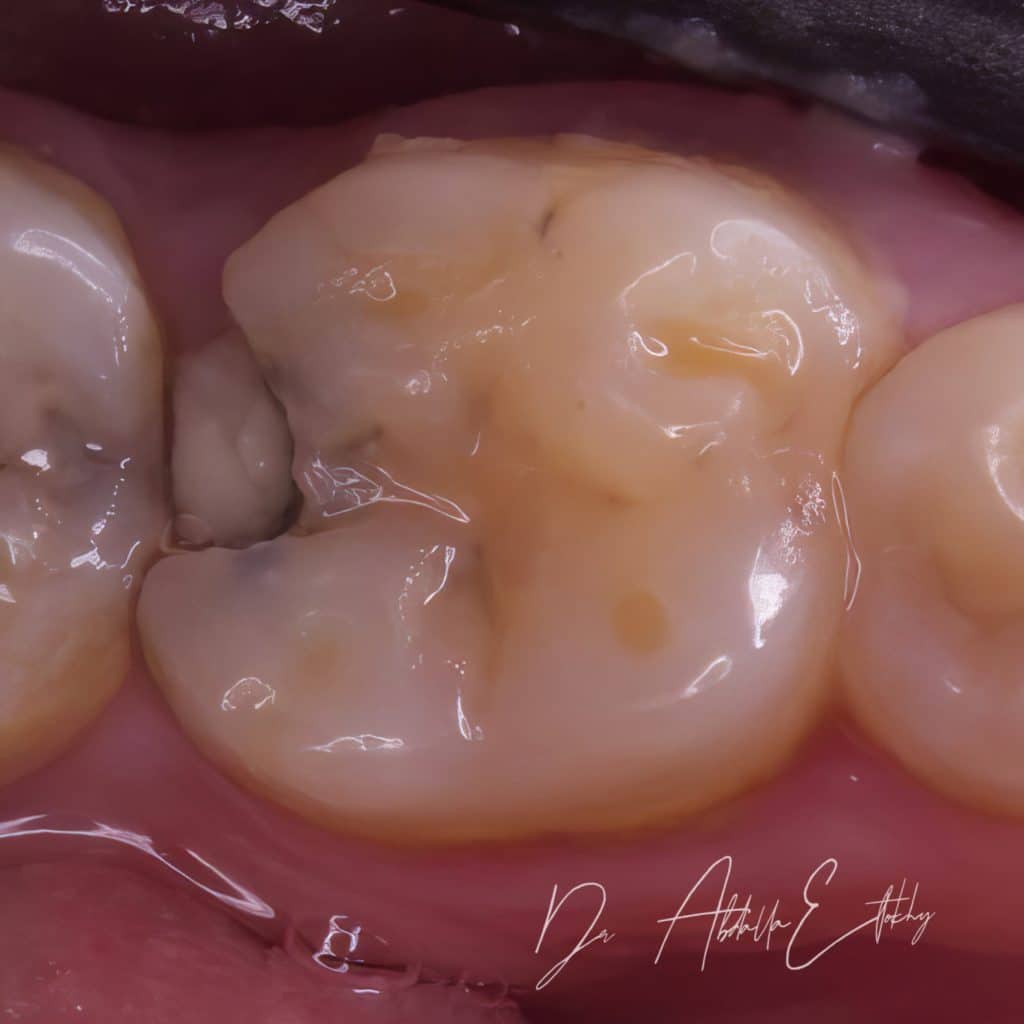

After clinical diagnosis & preoperative x-ray caries was close to the pulp but after taking history and doing vitality test with endo ice pt was suffering from hypremia so I started removing caries and selective caries removal was done to avoid pulp exposure then after getting a seal and drying cavity from bleed and doing etch and bond, small amount of flowable and packable was applied to ensure sealing and then RC was done then I waited about 5 min for maturation of hyprid layer then I continue elevating the margin and the restoration